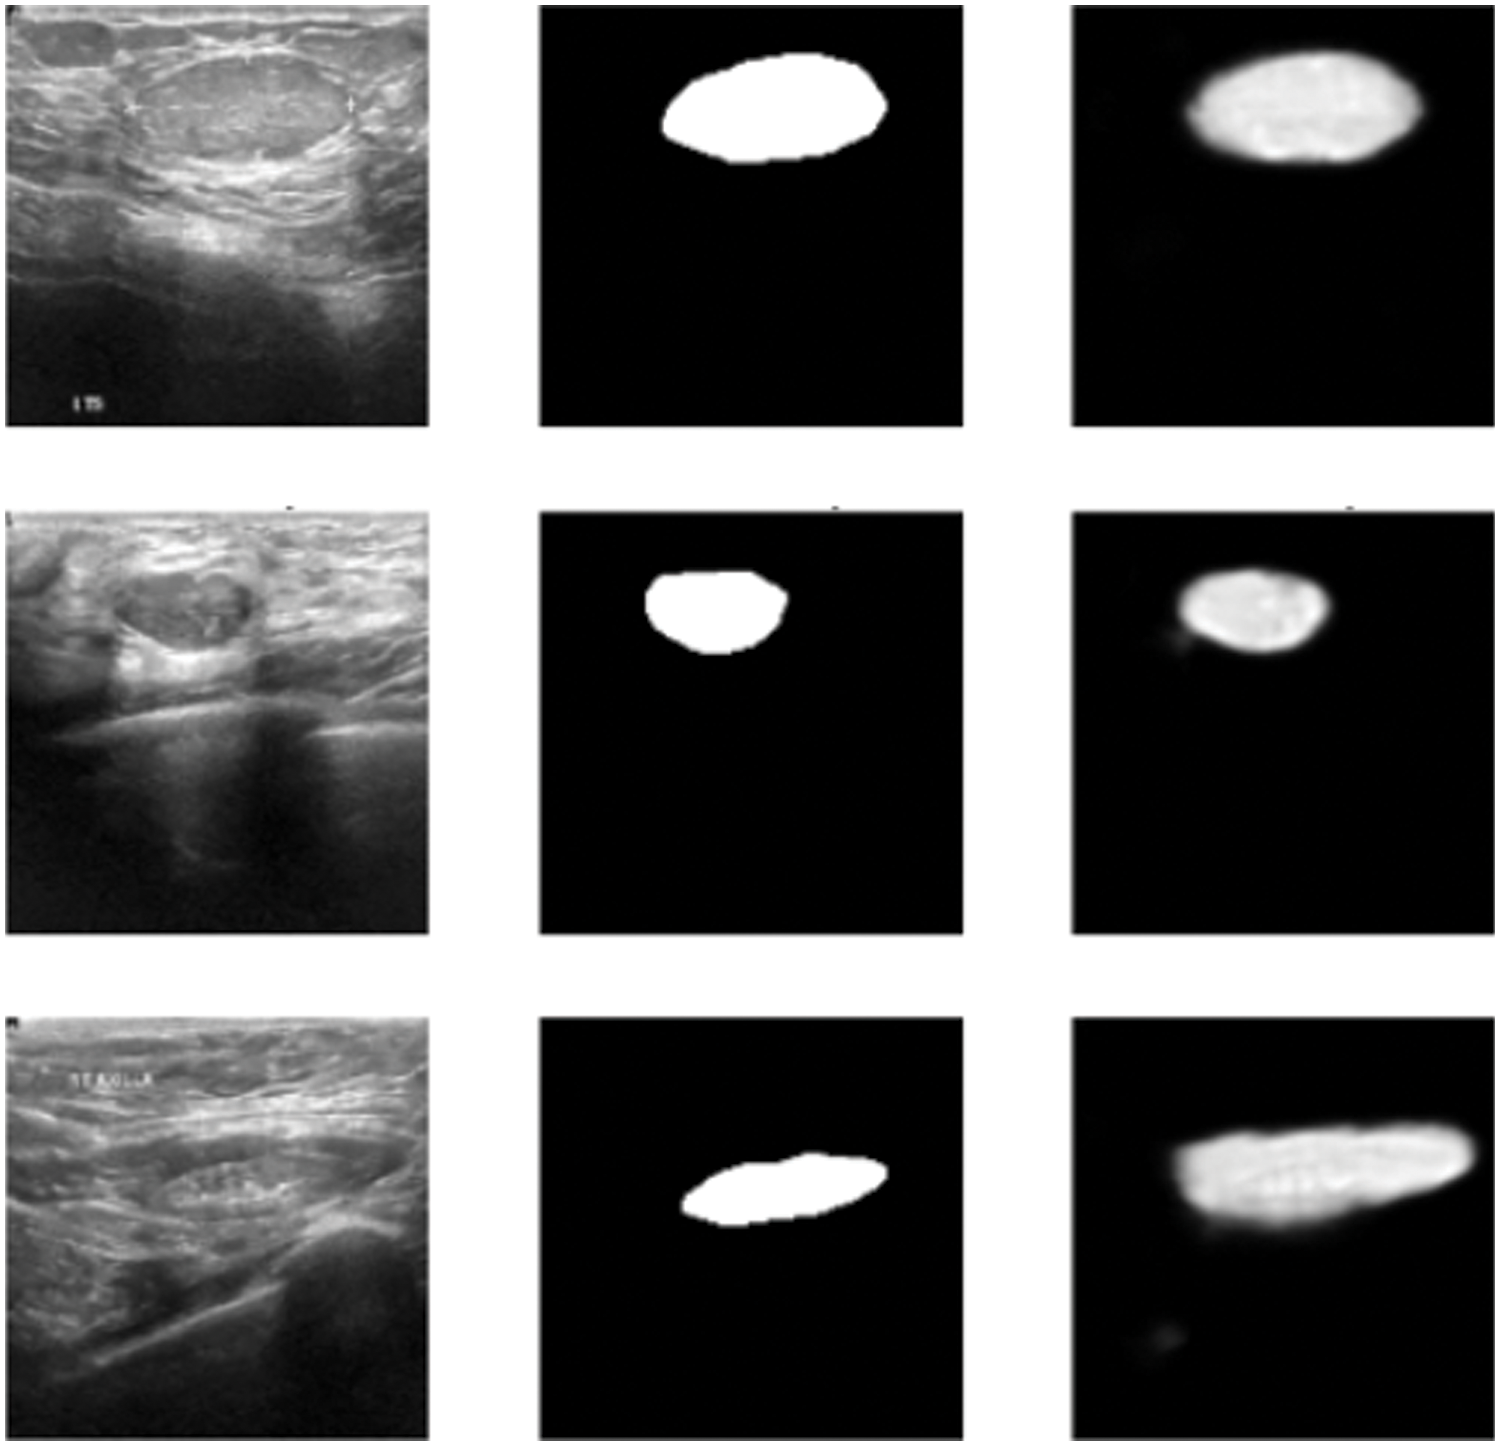

In this subsection, the framework shows the results after using U-Net architecture to segment the image after the process of denoising the image in the previous step. The U-Net model uses the result from the previous step after comparing the images of the five models and the level of noise. Tabs. 3 and 4 show the results after and before denoising the dataset of ultrasound, the results shows the enhancement of different metrics in the segmentation process after denoising the images, and the results also show the quality of u-net against the other methods, Fig. 10 shows the results of using U-Net in the segmentation process. The figure shows the ultrasound, mask, and predicted result using U-Net. Tabs. 5 and 6 show the results of classification of the segmented image into the malignant, tumor, and normal using different methods before and after removing noise, the results show the efficiency of methods after removing noise from images, and the results also show the efficiency of CNN against models. Fig. 11 shows the results of classifying the output into benign and malignant classes and Fig. 12 shows the results of removing noise in the enhancement stage.

Figure 10: Original ultrasound, mask, predicted mask respectively